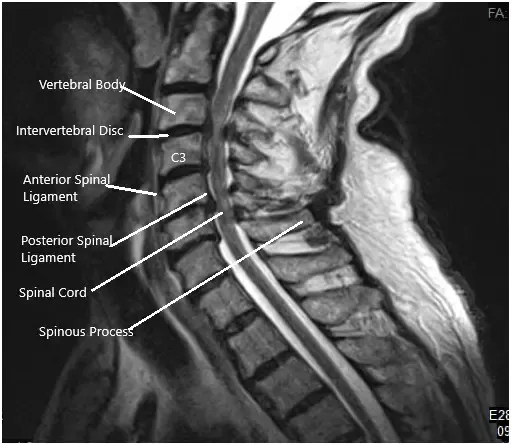

Una resonancia magnética de la columna cervical sugirió que en C3-4 hay una hernia discal central con estenosis grave del canal espinal y compresión moderada de la médula espinal cervical, con mielopatía compresiva. Se identifican protrusiones discales en C4-5 y C5-6 con un estrechamiento moderado del saco tecal y un leve aplanamiento/compresión de la médula cervical ventral. Estrechamiento leve del saco tecal en C2-3 y C6-7, con una pequeña protuberancia central en C2-3.

Resonancia preoperatoria en la sección sagital.